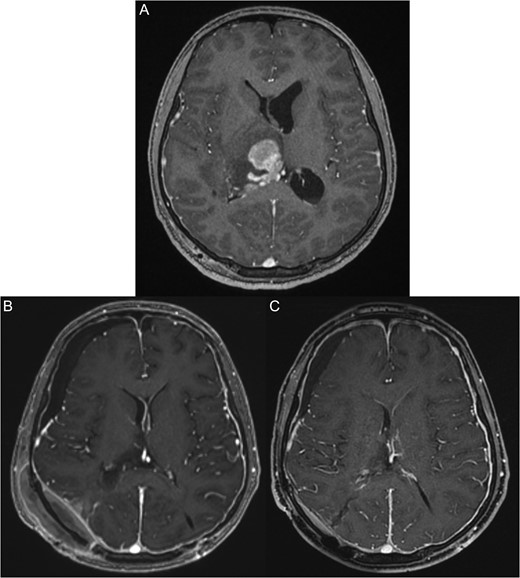

The patient was transferred to our institute for additional work-up. The patient was conscious on arrival to the hospital with a Glasgow coma scale of 15/15. His vital signs were stable with normal neurological examination. MRI revealed a large right thalamic lesion compressing the lateral ventricles (Fig. 1A).

(A) Pre-operative magnetic resonant imaging of the brain showing hyperintense large right thalamic lesion compressing the lateral ventricles. (B) Three days post-operative magnetic resonant imaging of the brain showing almost total resection expect few small inhasing nodules. (C) Two months post-chemotherapy and radiotherapy, magnetic resonant imaging show total disappearance of the mass and good radiological response.

The patient was transferred to the Oncology Department and received chemotherapy and radiotherapy with excellent radiological response. However, his left side weakness did not improve (Fig. 1B and C).